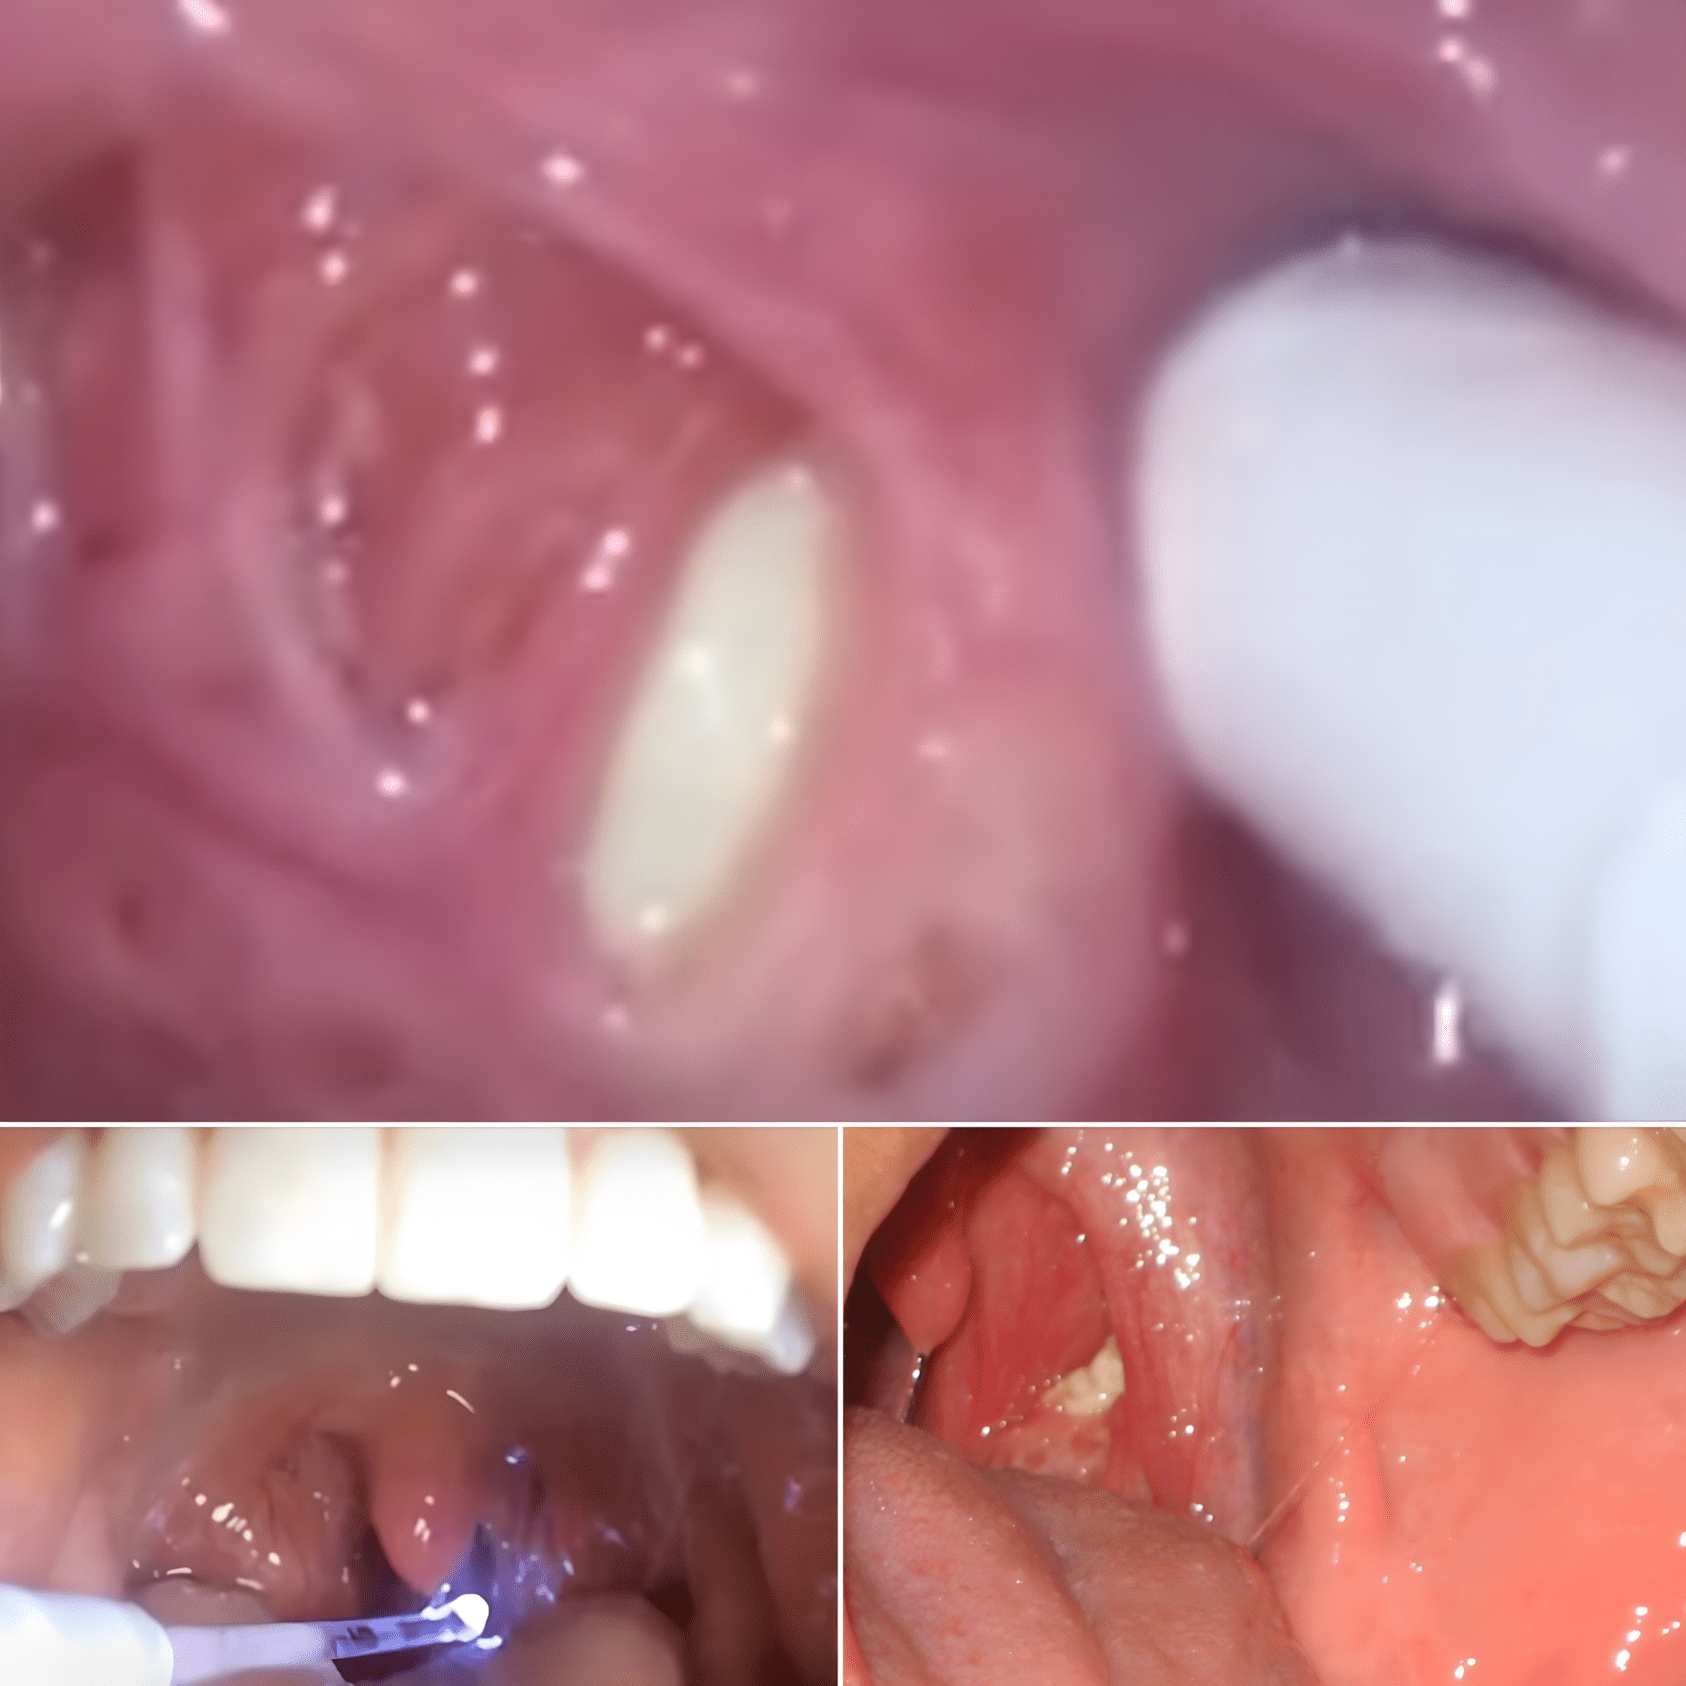

Wat zijn amandelstenen precies? Amandelstenen zijn harde, witte of gele formaties die zich op de amandelen vormen. Ze zijn meestal onschadelijk en kunnen vaak thuis behandeld worden, volgens de Mayo Clinic.